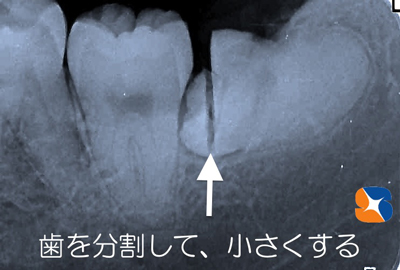

親知らずの歯の周囲の骨を削減し、歯を細かく分断させながら元の歯より小さい形に変えて抜きやすくしていきます。